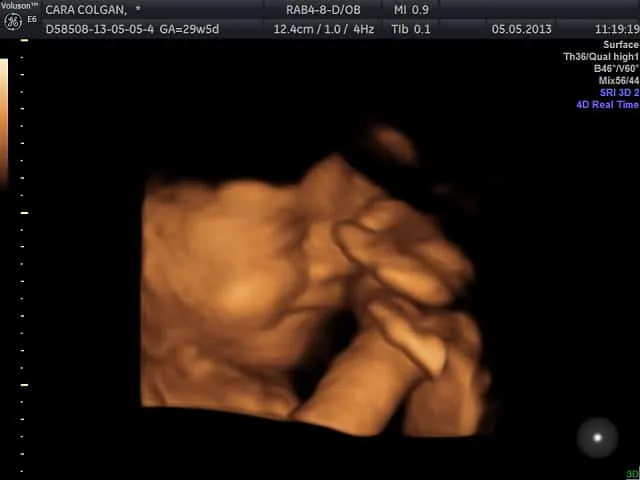

Dalam kajian dilakukan pengkaji daripada New Zealand pada 2005 menunjukkan video ultrabunyi bayi yang dianggap sedang menangis.

Beberapa pecahan dilakukan, melibatkan gerakan badan dan pernafasan bagi mengesahkan bayi dalam kandungan itu menangis.

Ini bermakna semasa membuat ujian ultrabunyi, anda mungkin melihat ekspresi wajah si comel berkerut, tetapi tiada bunyi yang didengar.